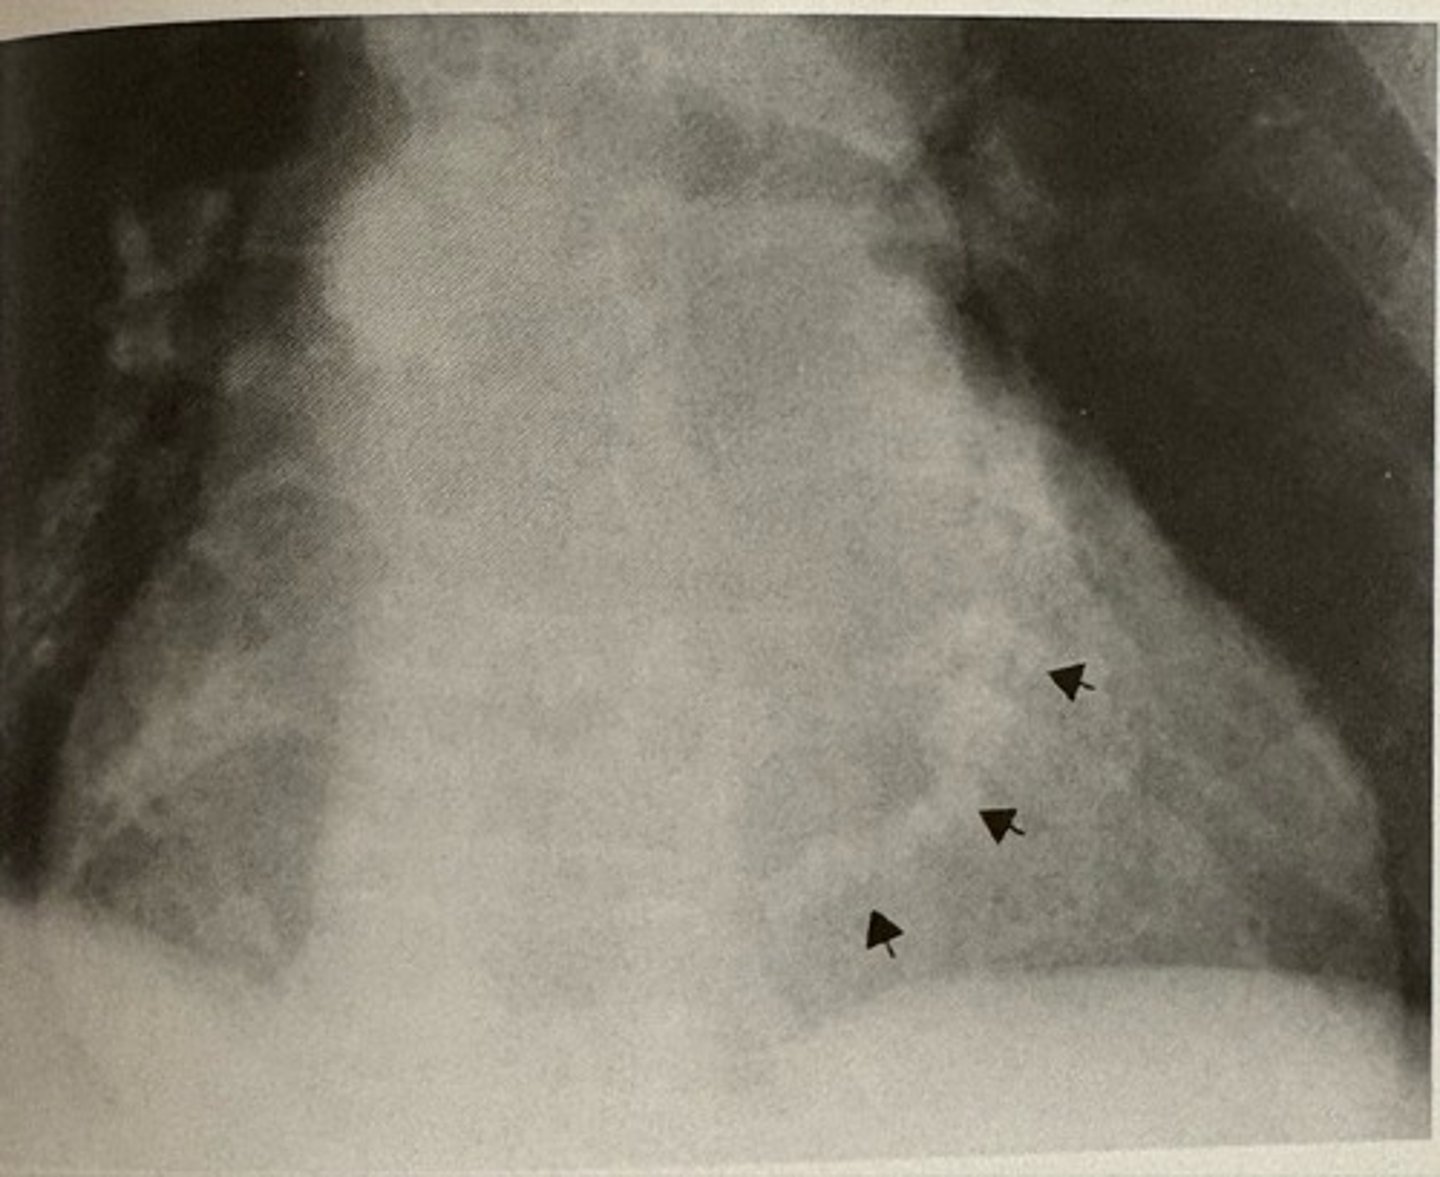

loculated pleural effusion (phantom tumor)

what pathology is present?